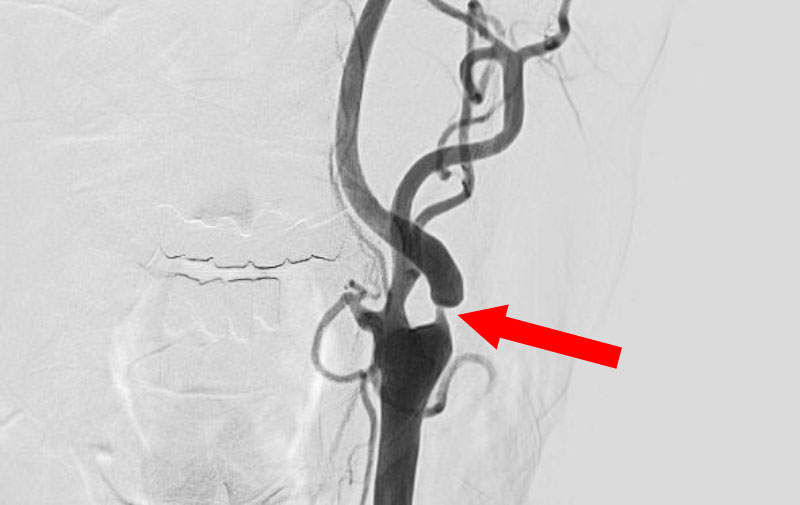

'24年10月

くも膜下出血

左内頚動脈後交通動脈

分岐部動脈瘤破裂

70代

救急外来

No.1509 手術前

No.1509 手術中

No.1509 手術後